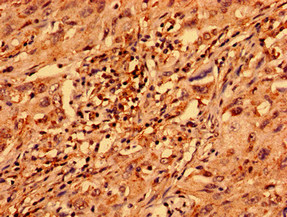

IHC (Immunohiostchemistry)

(Immunohistochemistry analysis of human lung cancer using AAA230297 at dilution of 1:100)